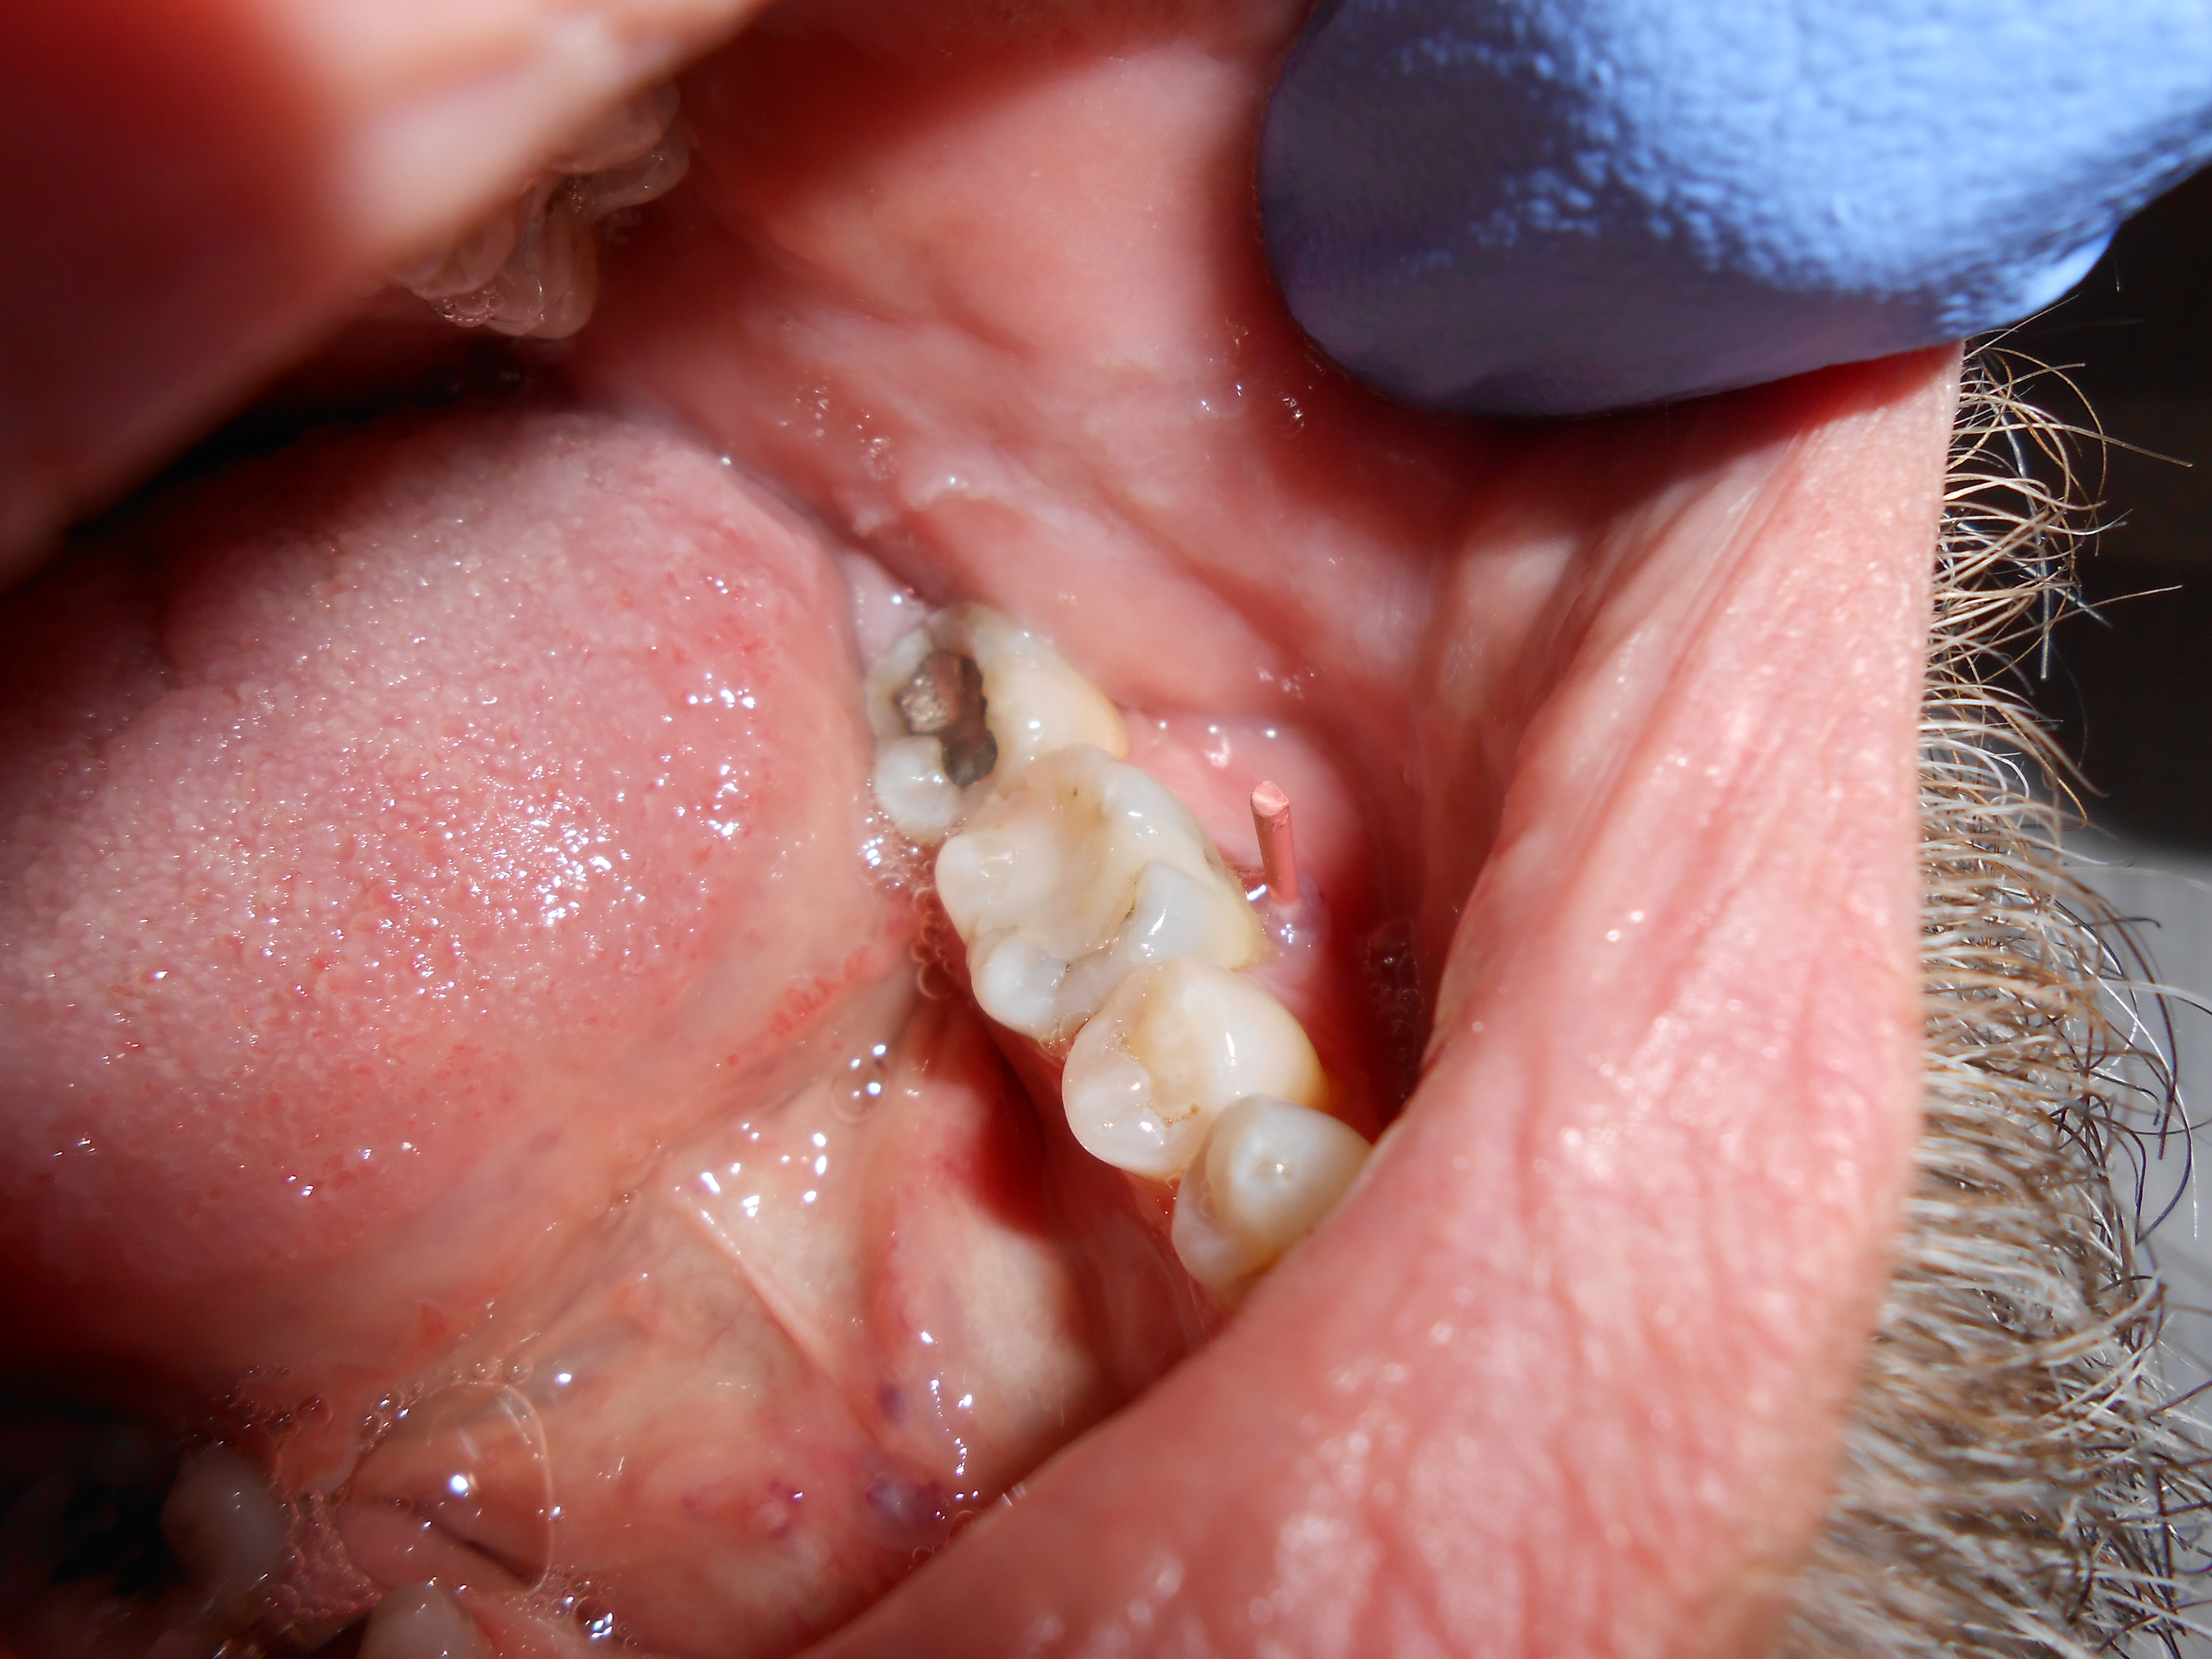

Chronic apical abscess is typically indicated by a radiograph that reveals a radiolucency. Clinically, there is a sinus tract present on the gingival tissue. It is paramount that the draining sinus tract be traced with a gutta-percha cone and then radiographed (Figure 3 and Figure 4).

Clinical confirmation of the periradicular diagnosis—chronic apical abscess on tooth No. 19. The tooth is not sensitive to percussion or palpation. A gutta-percha #25/.04 cone is inserted into the sinus tract.

Figure 3